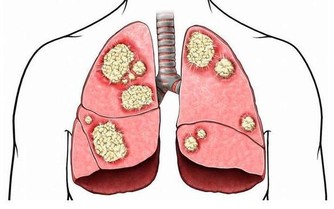

*****咳嗽與咳痰*****

感冒初期的咳嗽以乾咳為主,是一種防禦動作,通過咳嗽清除呼吸道內異物(病菌),一般不建議針對處理。當咳嗽頻繁影響工作或休息,才需處理。

正常人的痰液為泡沫狀或黏液狀,當痰量增多則是病態現象,看痰的性狀提示的疾病:

清色或白色痰:為病毒感染居多,也可見於支氣管炎、肺炎初期;

金黃色濃痰:提示金黃色葡萄球菌感染;

鐵鏽色痰:為肺炎球菌肺炎的典型特徵;

黃綠色或翠綠色痰:提示銅綠假單胞菌感染;

痰白粘稠且呈絲狀:提示真菌感染;

粉紅色泡沫痰:提示肺水腫,見於心功能衰竭者;

痰惡臭:提示厭氧菌感染。

治療,乾咳可以適當服用止咳藥物,針對乾咳的藥物有福爾可定口服液、氫溴酸右美沙芬、枸櫞酸噴托維林等;咳痰不能服用止咳藥物,易存在痰液殘留加重感染,可服用祛痰藥物,讓痰液咳出,常用的祛痰藥物有:氯化銨、溴己新、氨溴索、乙酰半胱氨酸、羧甲司坦等。祛痰藥使用後可出現咳嗽加重,為排痰作用。